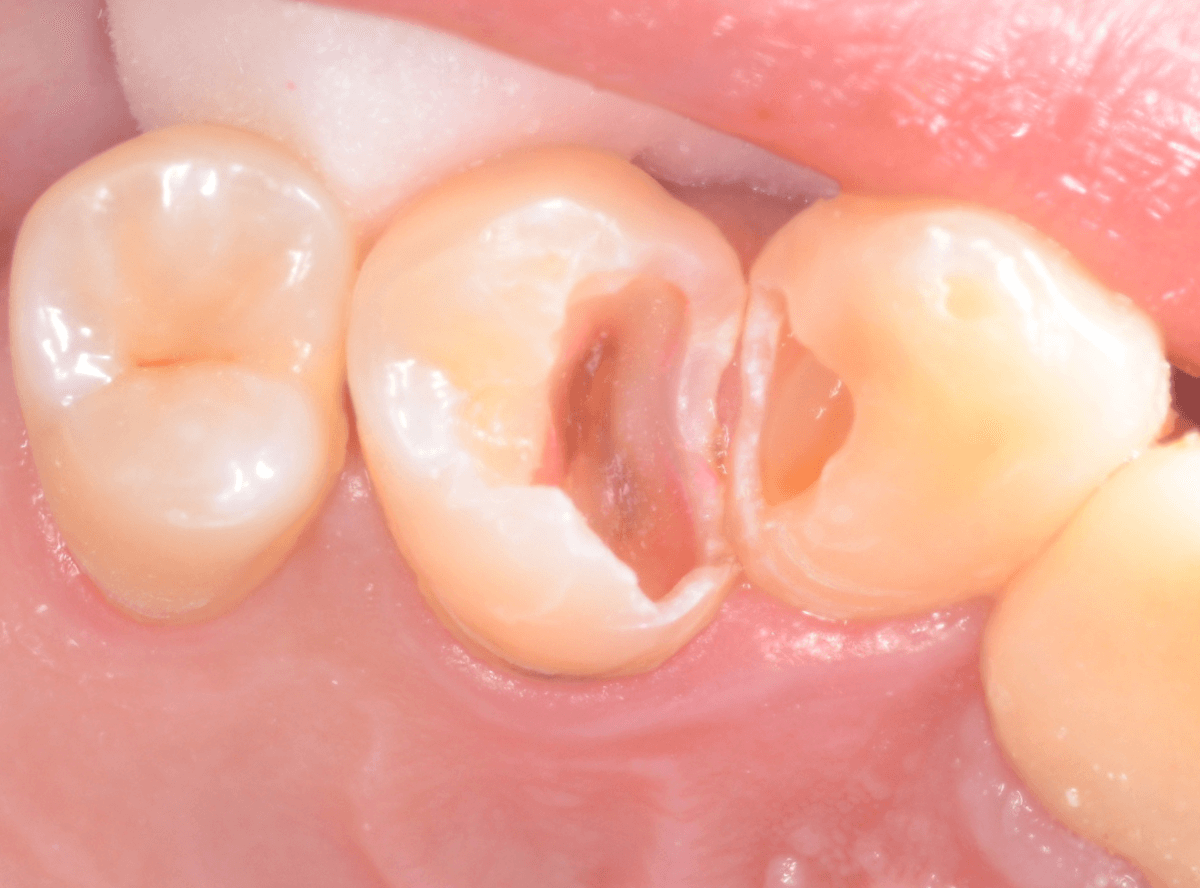

Case.21 神経に達しそうな2本の大きな虫歯

上の小臼歯の側面が明らかに虫歯になっている患者さんです。

患者さんは特に症状を感じてなさそうですが、恐らくは中で大きな虫歯になっているでしょう。

このように、自覚症状からだけでは虫歯の状況は診できません。

レントゲン写真で確認します。

青い線が歯の神経、赤い線が虫歯と思われる部分です。

2本とも、神経に達してしまいそうな大きな虫歯であると思われます。

まず、奥の歯のつめものを外してから、虫歯の治療を開始します。

手前の歯が大きな虫歯が見えてきました。